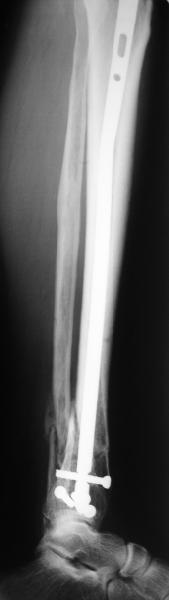

A typical case is attached, also an image with intra-op reduction obtained by a small wire distractor, in the moment of insertion a Poller wire in AP direction. Fixation by a SIGN nail. Despite the fibula was not fixed healing was obtained with the unchanged alignment.

Very interesting application, but is the final position in a little distal varus with some fibula

distraction? Would that have been eliminated by fibula plating?

At least both the ankle mortise and tibial alignment look acceptable, don't they?

I am just trying to illustrate that prevention of 1)tibial valgus and 2)loss of reduction can be provided without fibular plating. Small changes of conventional nailing techniques allow to maintain reduction of the tibia reliably without adjunctive fibular stabilization.